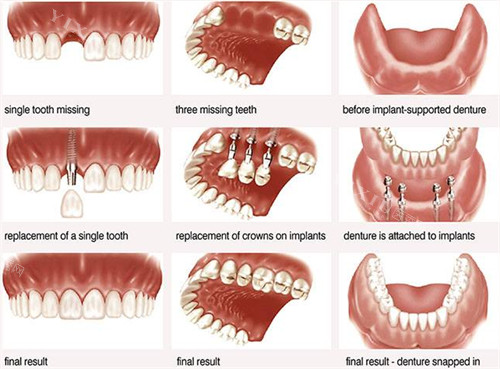

一、单颗种植牙价格:从国产到进口,品牌决定费用

国产植体:性价比之选

国产种植牙价格相对亲民,适合预算有限的患者。以雁塔区某连锁口腔机构为例,国产植体单颗价格集中在5000-8000元区间,部分机构推出集采价套餐,比较低可至4000元/颗(含植体+基台+牙冠)。

进口植体:品牌与技术的双重溢价

进口植体因材质、工艺和临床数据差异,价格跨度较大。雁塔区主流进口植体价格如下:

二、半口/全口种植牙价格:技术决定方案,方案影响费用

半口或全口缺牙患者需根据牙槽骨条件选择种植方式,费用因技术复杂度差异显著。

半口种植牙:4-6颗植体支撑

传统固定桥修复:需植入4-6颗植体,搭配烤瓷或全瓷桥,费用约2.5万-5万元;

All-on-4/6即刻种植:通过斜向植入技术减少植体数量,即刻负重,费用约4万-8万元(含植体、桥架及牙冠);

分段式种植:分两次植入植体,适合骨量不足患者,费用约3万-6万元。

全口种植牙:8-12颗植体支撑

传统全口固定修复:需植入8-12颗植体,费用约6万-12万元;

All-on-4全口即刻种植:上下颌各植入4颗植体,费用约8万-15万元(含植体、桥架及牙冠);

个性化种植方案:根据牙槽骨三维扫描数据定制植体位置,费用约10万-20万元。

品牌选择:半口/全口种植牙常用植体品牌包括韩国登腾、美国皓圣、瑞士ITI、瑞典诺贝尔等,高端品牌因骨结合稳定性更优,价格普遍高于中低端品牌。